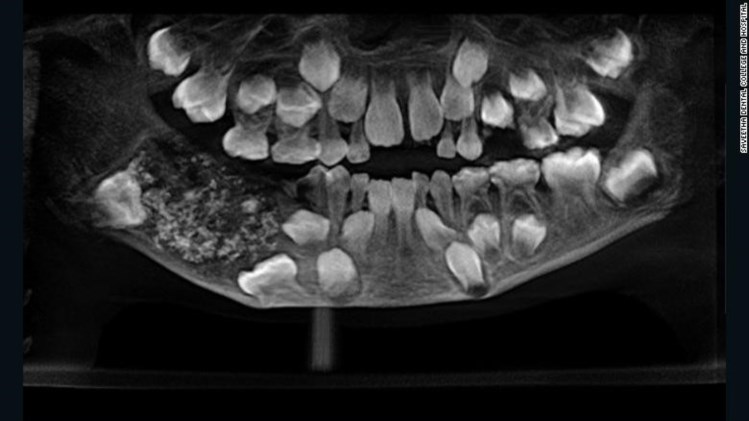

Um menino indiano de sete anos queixava-se de dores fortes no maxilar quando chegou ao hospital da cidade de Chennai, no sul da Índia. Depois de observarem um raio x, os médicos encontraram 526 dentes dentro de uma espécie de “bolsa” que estava embutida no maxilar inferior.

A diretora do departamento de Patologia Maxilofacial e Oral do Hospital de Saveetha, Prathiba Ramani, disse à CNN que os dentes tinham tamanhos “entre 0,1 milímetro e 15 milímetros”, mas todos tinham coroa, raiz e esmalte.